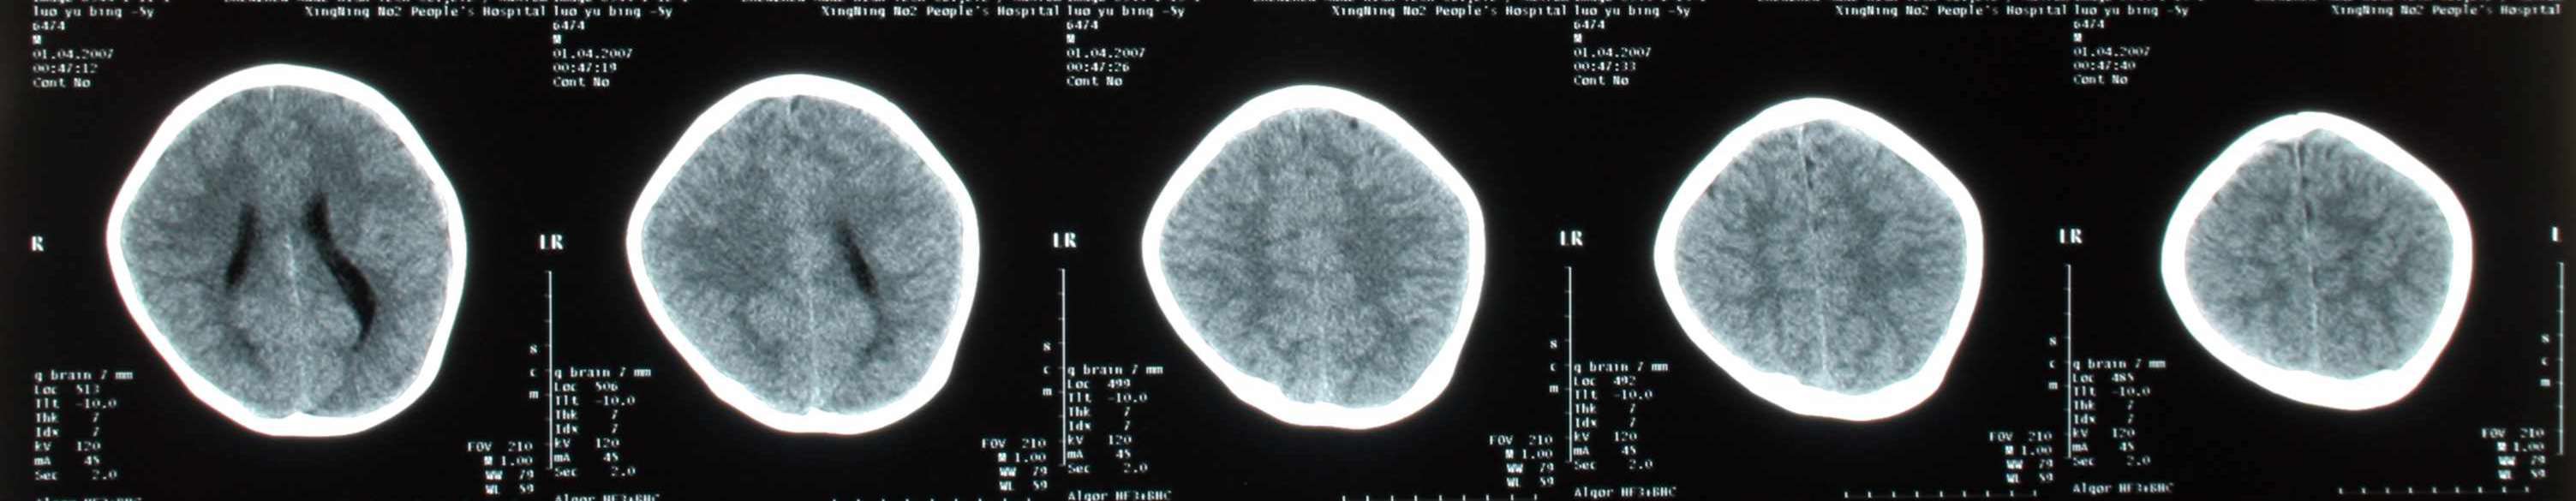

患儿,男,3周岁,半小时前不慎从床上摔下来,当时前额着地,后诉有点痛,伴呕吐二次,请各位老师会诊,患儿头颅有没有问题,后枕部颅下密度增高影,是伪影还是有出血,请指点:

未见明显异常(脑灰白质分界清晰,脑池、脑室无扩张、变形、移位)。